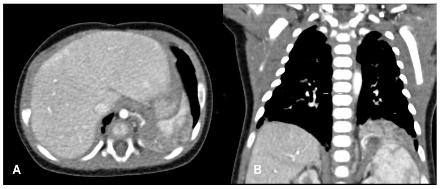

Figure 2. Congenital pulmonary malformations with large and small cystic areas of hyperinflation. No systemic irrigation was observed.

In the postnatal period, the gold standard remains contrast-enhanced computed tomography (CT angiography), which enables high-resolution evaluation of the bronchial tree integrity, characterization of parenchymal architecture (Figure 4), and assessment of the number and size of cysts (Figure 2). It also allows for precise visualization of aberrant systemic vessels (Figure 5), as well as evaluating compressive effects on mediastinal structures.